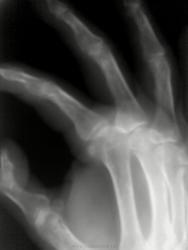

Женщина 1952г.р. Более 10 лет страдает подагрой. В мае была травма сухожилий кисти, сейчас беспокоят боли в области пястно-фалангового сустава 2 пальца.

Коллеги, так все же, данную клинику, на ваш взгляд, обуславливает подагра или последствия травмы в анамнезе.

Трудно, что-то сказать, четкости на изображениях нет.

Дело в том, что откладывание кристаллов моноурата натрия локально при подагре ни когда не происходит, как правило это "системно"(в плане поражение мелких суставов), а обычно поражаются плюснефаланговые суставы первого пальца обеих стоп. Вообще в конкретном случае для Вас ясно что пациент с подагрой, в любом другом случае идет дифференциальная диагностика с ревматоидным артритом.

Наличие подагры сомнений не вызывает. Вопрос в том что является причиной клиники: подагра- артрит; следствие травмы в анамнезе?

Как врач клиницист(при наличие фотоснимка): явно наличие тофуса, как к врачу-рентгенологу могут возникнуть вопросы, именно поэтому следует сделать снимки аналогичной кисти. В данном случае костно-травматические изменения можно исключить, ибо клинически изменения были бы на глаз.